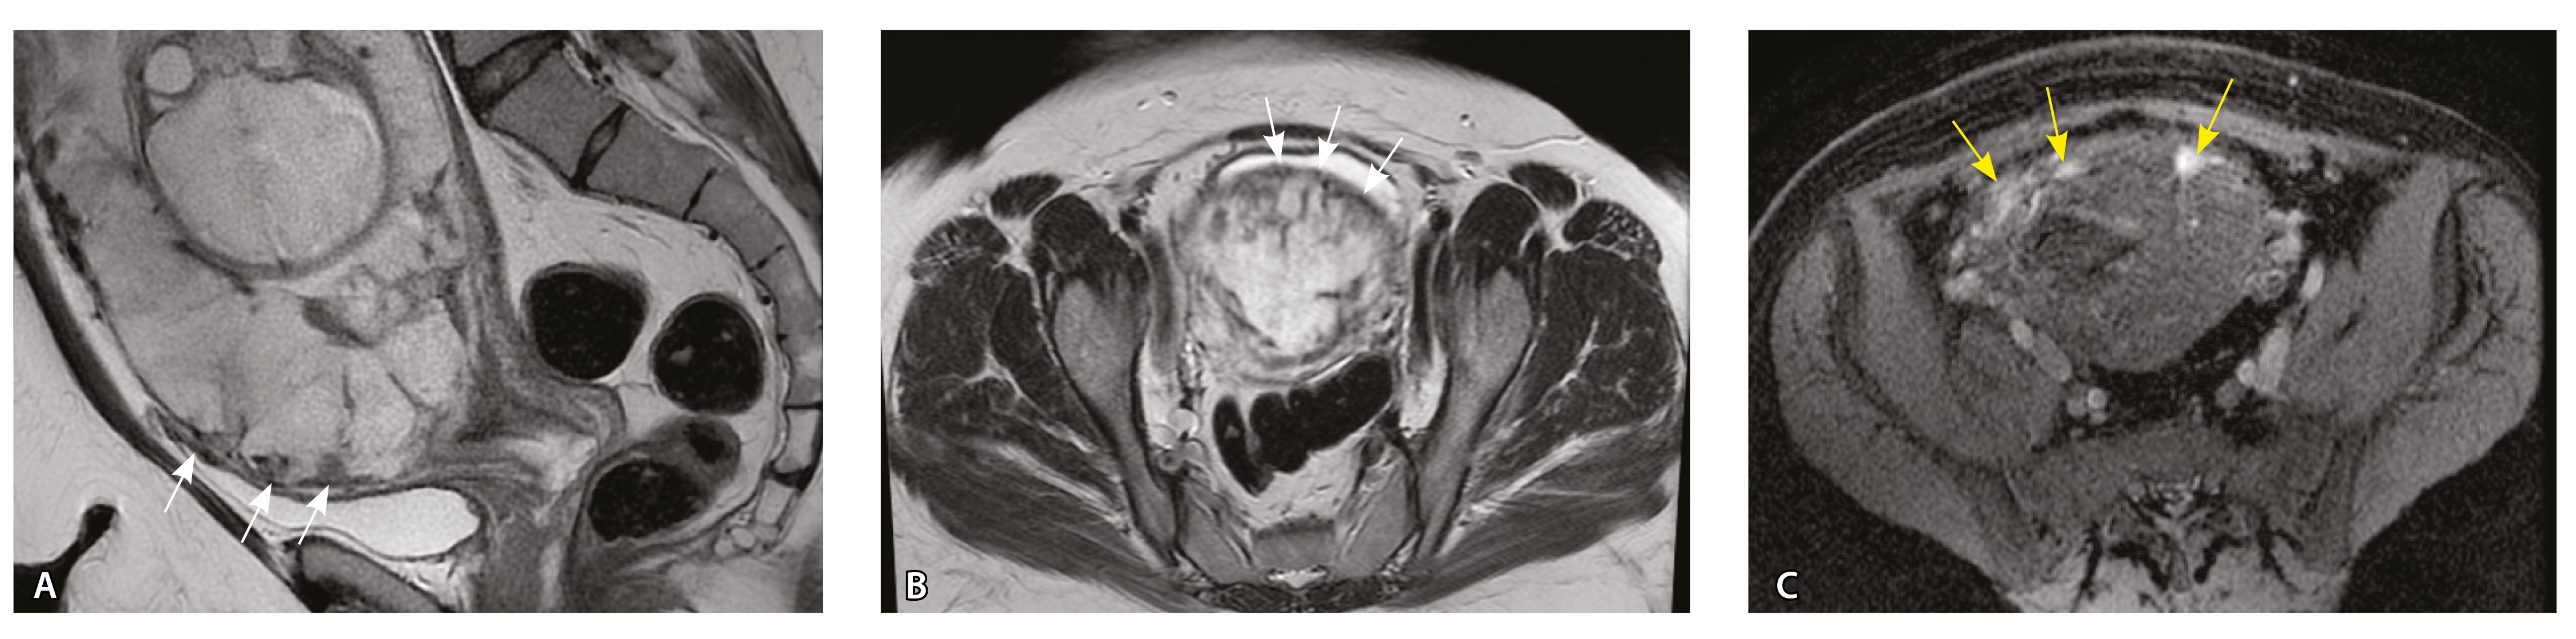

Рис. 2. Беременность 32 недели, центральное предлежание плаценты без признаков приращения. На магнитно-резонансных томограммах в режиме Т2-взвешенного изображения (Т2ВИ) в сагиттальной плоскости (А) и Т2ВИ с подавлением сигнала от жировой ткани во фронтальной плоскости (Б) видны мелкие ретроплацентарные сосуды, расположенные на границе плаценты и рубца на матке от кесарева сечения (белая стрелка) либо плаценты и миометрия (желтые стрелки; плацентарная площадка указана белой пунктирной линией). Фото микропрепарата: В – визуализируются мелкие артерии и вены в составе серозной оболочки, стрелкой указан слой мезотелия (окраска азокармином по Маллори; × 50); Г – маточно-плацентарный сегмент, стрелкой указан сосуд в толще миометрия на границе с плацентой (окрашивание гематоксилином и эозином; × 50)

В смежных участках строение стенки матки было представлено миометрием с разной ориентацией мышечных пучков и тонкими соединительнотканными прослойками. Сосудистая система состояла из синусоидов – тонких полостей в срединном слое миометрия, а также пре- имущественно мелких артерий в составе серозной оболочки. Только единичные из них визуализировались на МРТ, так как данным методом ввиду технических особенностей невозможно визуализировать самые мелкие сосуды и серозную оболочку матки из-за ее малой толщины. Тем не менее это важно для сравнения картины нормы с последующей гиперваскуляризацией при различных степенях PAS.